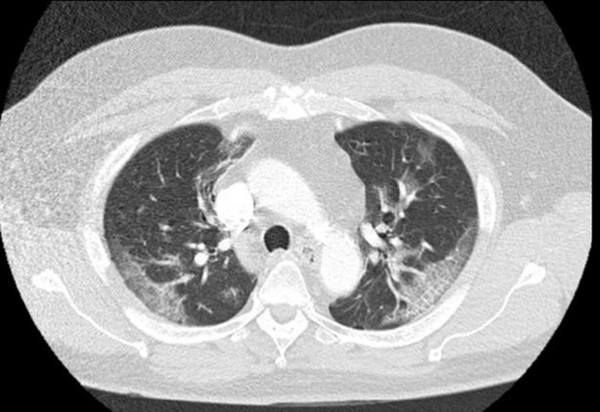

Hình chụp phổi cho thấy trong phổi của ông có những vết mờ đục như thủy tinh vỡ vụn. Bởi vậy, ông được cách ly và xét nghiệm COVID-19. Sau đó, thân nhiệt của ông tăng lên 38,4oC.